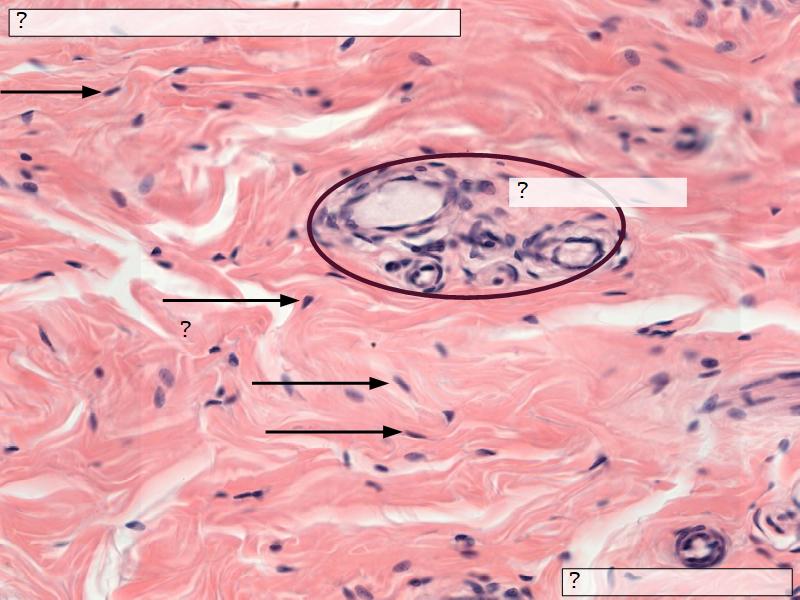

Stroma

- Collagenous connective tissue

- Irregular dense connective tissue

- Smooth muscle

- Fibres and bundles

- Lactiferous sinusses

- Stratified cuboidal epithelium